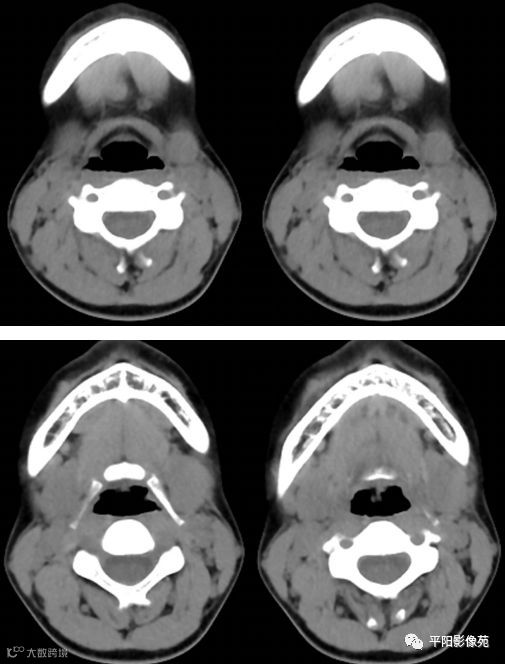

影像表现:

CT:左侧颌下腺增大,其内后下方可见类圆形等密度影,增强扫描轻度强化,动脉期CT值约50Hu,静脉期CT值约61Hu,边界欠清,大小约1.6cmX1.3cm。增强扫描右侧颌下腺形态完整,密度均匀,边缘光滑,周围脂肪间隙清晰,颈I区可见明显肿大淋巴结,较大者约1.0cmX0.8cm。